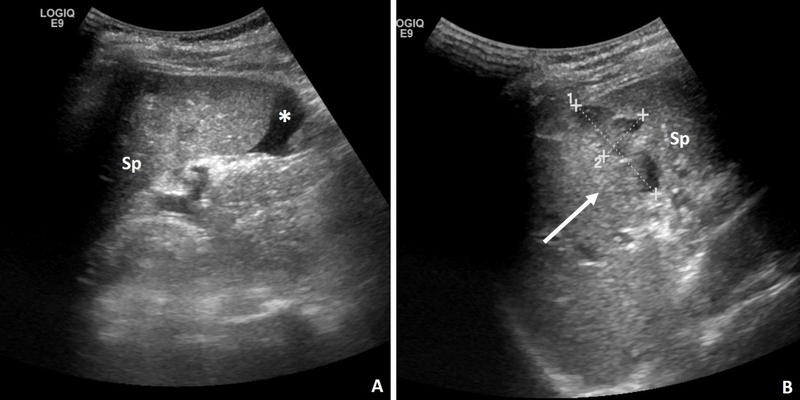

Siêu âm lách: Siêu âm lách qua kẽ liên sườn có thể đo được kích thước của lách.

Lách to có mấy độ, phân biệt như thế nào? 3 Hình ảnh kết quả siêu âm lách